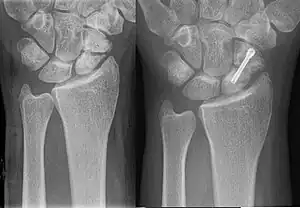

Hypertrophic non-union

Callus is formed, but the bone fractures have not joined. This can be due to inadequate fixation of the fracture, and treated with rigid immobilisation.

.jpg.webp)

Types of Nonunion

Judet and Judet, Muller, Weber and Cech, and others classified nonunions into two types according to the viability of the ends of the fragments: Hypervascular nonunions and avascular nonunions.

Hypervascular nonunions are subdivided as:

- "Elephant foot" nonunions: These are hypertrophic, rich in callus and are a result of inadequate immobilisation, insecure fixation or premature weight bearing.

- "Horse hoof" nonunions: Mildly hypertrophic, poor in callus and is due to unstable fixation.

- Oligotrophic nonunions: They are not hypertrophic but vascular, no callus seen and is due to severely displaced fracture or fixation without accurate apposition of fragments.